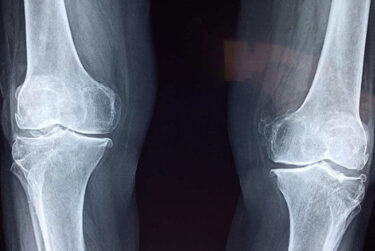

It’s not too late though and every year, the Tour de France provides great inspiration for thousands of people to get back into cycling. Riding a bike is a great way to exercise, but if you’ve recently had a knee replacement operation how should you get back in the saddle? Join us as we look at some top tips on cycling after knee replacement surgery.

Cycling after a knee replacement is possible and in many cases even recommended once approved by your doctor. It’s a good idea to start with a stationary bike around 2–6 weeks after surgery before progressing to outdoor rides after about 12 weeks. The aim is to gradually build strength, flexibility, and distance.

Can I cycle after a knee replacement?

Getting back into cycling after knee problems, knee injuries, or joint replacement surgery requires some care. However, it’s perfectly possible if your overall health allows and your doctor has given you the go-ahead. After all, there are plenty of athletes that have had knee replacements! And if they can do it, why can’t you?

For the first couple of weeks after knee arthroscopy or knee replacement surgery, your priorities will be decreasing the swelling around your knee and attaining a full range of motion. While cycling is recommended as an effective form of exercise after knee surgery, returning to the bike depends on your post-surgery mobility.